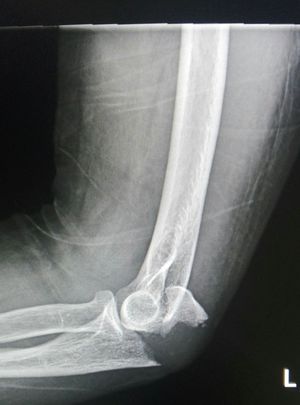

Right elbow lateral View

Olecranon Fracture.